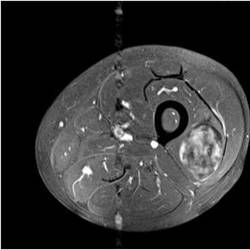

Physician Assistant Lower Limb and Thorax Written Examination - Radiology Pool

Gallery of Unlabled Radiographs from Lecture (Dr. French) - 2020

Click a thumbnail to enter the gallery display. Click the file name link at the bottom left of the gallery display to view the image at high resolution.